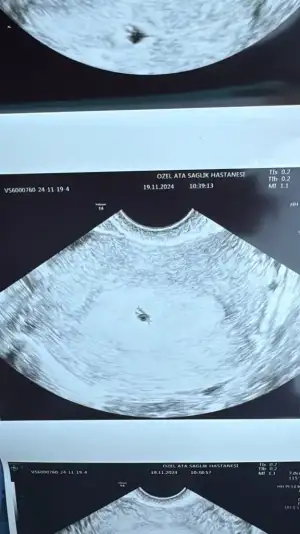

Bugün 4 hafta 6 günlüğüz ve çok şükür kesemiz göründü

• 1BC37048-C990-4786-BF49-3800BBF70064.webp

32,2 KB · Görüntüleme: 62